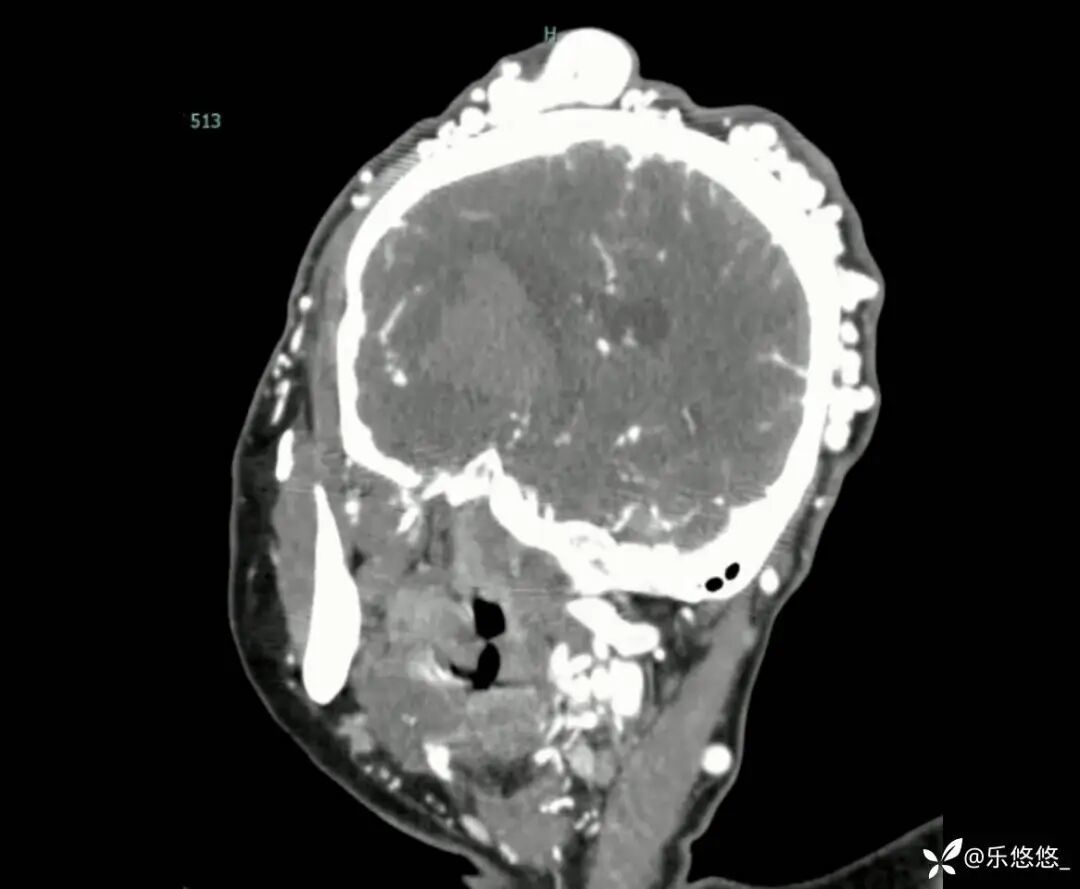

头部 CT 平扫显示右侧基底节区脑实质内出血,大小为 4.2x2.6cm,压迫右侧侧脑室。头皮不规则,可见多发类圆形和管状病变。

三维重建 CT 血管造影显示:头皮软组织层有多条扩张、迂曲的静脉血管。